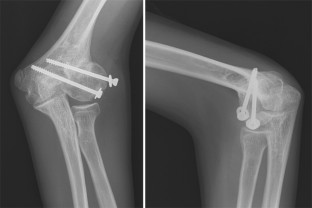

Die Pseudarthrose des kindlichen Condylus radialis humeri mit posttraumatischem Cubitus valgus stellt nach inadäquater Behandlung eine ernsthafte Komplikation dar. Wir berichten über einen damals 14-jährigen männlichen Patienten, der nach konservativer Frakturbehandlung des Condylus radialis humeri eine zunehmende Fehlstellung im Sinne eines Cubitus valgus entwickelte. Nach Durchführung einer Schraubenosteosynthese wurde nach gesicherter Konsolidierung eine erfolgreiche suprakondyläre Domosteotomie vorgenommen, die zur Beschwerdefreiheit und freien Beweglichkeit des Ellenbogengelenks führte.

Non-union of the pediatric lateral humeral condyle following post-traumatic cubitus valgus is a severe complication after inadequate treatment. We report on a then 14-year-old male patient who developed an increasingly defective position in terms of cubitus valgus after conservative treatment of a lateral humeral condyle fracture. After performing screw osteosynthesis and achieving consolidation, a successful supracondylar dome osteotomy was performed which led to relief from pain and free range of motion of the elbow joint.

Abb. 2